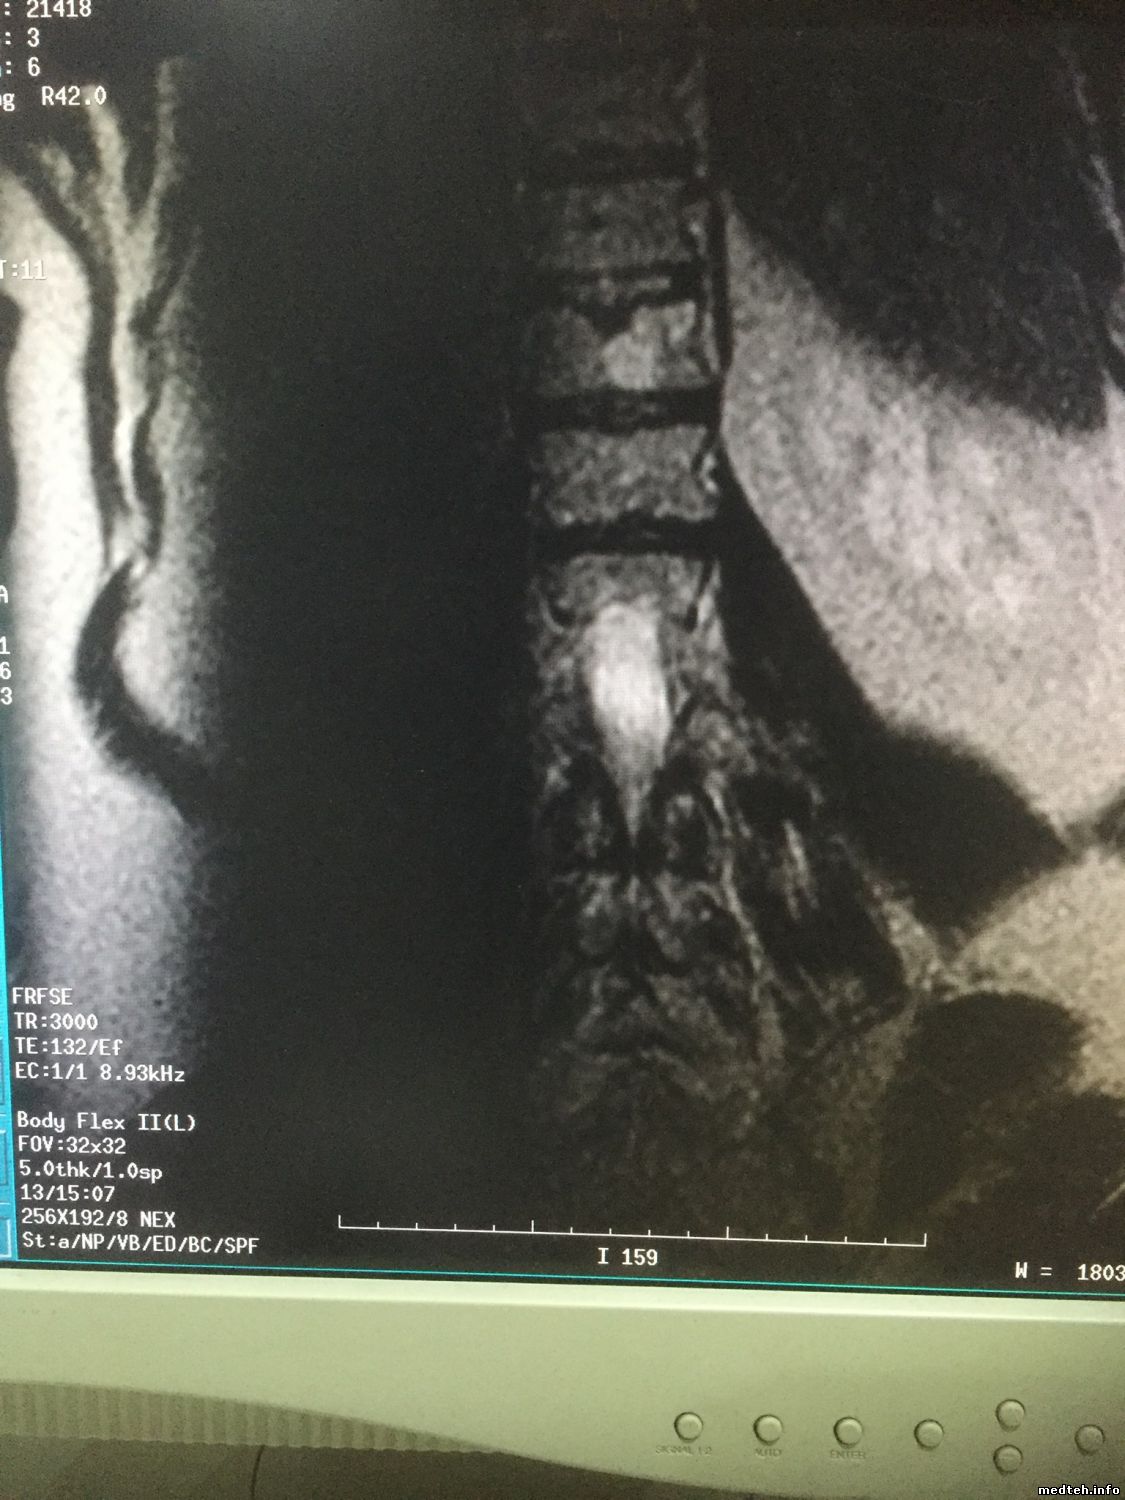

на продольном боковом срезе брюшной полости (катушка BodyFlex ) рядом с позвоночником слева вертикалный дефект картинки в виде темной полосы с размытыми краями... причина?

картинки такие:

1400157.jpg (85.3 Kb) · 5506200.jpg (95.1 Kb) · 2307948.jpg (156.9 Kb) · 2009293.jpg (158.7 Kb)

на мой взгляд, это потеря сигнала из-за наложения срезов.. смотреть чисто геометические параметры: матрицу, размер вокселя, расстояние между срезами, толщину среза.

Коллеги, закрадывается у меня мысль, что это очень напоминает сатуратор, который случайно выставили и забыли, насколько помню есть сатураторы которые не отображаются в виде сеточки, их просто в самом протоколе можно активировать и задать координаты, а тут просто как будто активировали и по умолчанию выставилась координата. Точно знаю, что на сосудах есть такие сатураторы, чтобы допустим, отсекать сигнал от вен и получать сигнал только от артерий. По маркировке, если память не изменяет по направлению фазы кодирования, ну что-то типа А или S. Попробуйте посмотреть в настройках самого протокола. Я ведь правильно понял, что это только в этой программе, такая фигня?

Да вроде на картинке пишет, что аж 3000 TR...

Мля, это какой-то добрый человек перекрутил сагиттал с сатуратором на потрохах в коронал. Не выключая сатуратор.